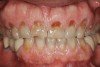

Figure 2   Asymmetric tooth wear in a bruxism triad patient as a result of friction from bruxing, poor salivary lubrication as a byproduct of medication, and roughened surfaces created as a result of erosive reflux.

Figure 2

The study of tooth wear is appropriately described as tribology: the science of interacting surfaces in relative motion and associated issues of lubrication, friction, and wear. Teeth sliding over each other are affected by a complex tribological interaction. Friction is encountered whenever there is relative motion between contacting surfaces, and it always opposes the motion. As no surface is perfectly smooth, when the teeth make contact, even under light load, it may produce the loss of tooth structure. When non-roughened surfaces contact, their coefficient of friction decreases dramatically if a lubricant is introduced. Tribology would suggest that a decrease in oral lubrication coupled with tooth-on-tooth contact would introduce friction and, thus, wear.12 In addition, elements that increase the surface roughness (eg, erosion) would unavoidably increase wear (Figure 2).